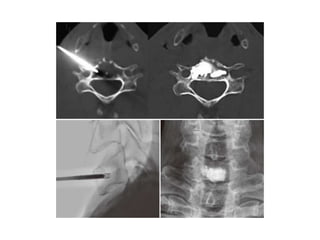

Anterior Cervical Approach

Manual displacement of the carotid–jugular complex

Guide needle insertion

Needle position can be confirmed with CT.

Cervical Vetebroplasty

C3 VP for metastasis

The needle was inserted with finger compression of the visceral tissue (left).

Bone cement was injected into the C3 vertebral body, and

simultaneously an esophagogram was performed to check the

esophageal injury (middle). Postoperative lateral view (right).